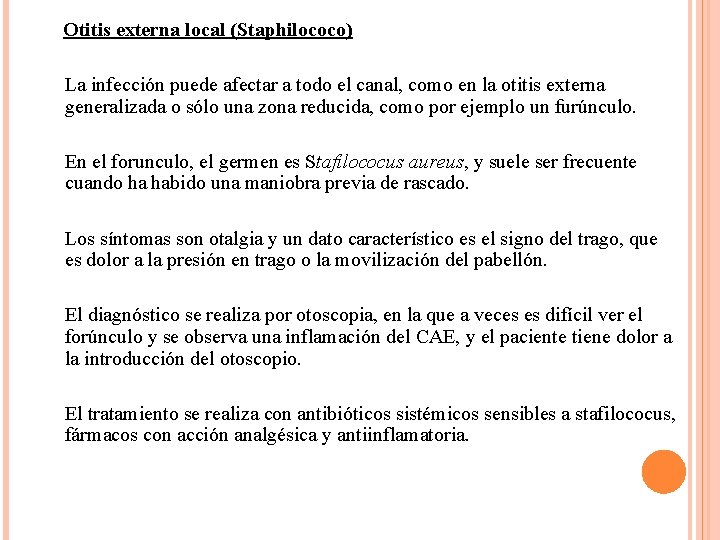

Otitis externa local (Staphilococo) La infección puede afectar a todo el canal, como en la otitis externa generalizada o sólo una zona reducida, como por ejemplo un furúnculo. En el forunculo, el germen es Stafilococus aureus, y suele ser frecuente cuando ha habido una maniobra previa de rascado. Los síntomas son otalgia y un dato característico es el signo del trago, que es dolor a la presión en trago o la movilización del pabellón. El diagnóstico se realiza por otoscopia, en la que a veces es difícil ver el forúnculo y se observa una inflamación del CAE, y el paciente tiene dolor a la introducción del otoscopio. El tratamiento se realiza con antibióticos sistémicos sensibles a stafilococus, fármacos con acción analgésica y antiinflamatoria.